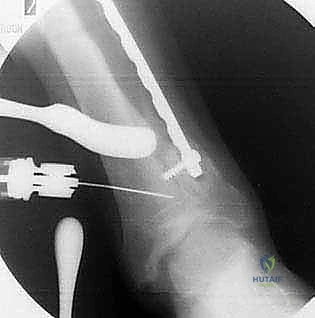

استخدام الشرائح والمسامير لتثبيت العظم

4. قطع العظم (The Osteotomy)

هناك تقنيتان رئيسيتان يختار الدكتور هطيف بينهما بناءً على حالة المريض:

* تقنية الوتد المفتوح (Opening Wedge): يتم عمل شق في العظم وفتحه لإضافة طعم عظمي (صناعي أو من حوض المريض) لتعديل الزاوية.

* تقنية الوتد المغلق (Closing Wedge): يتم إزالة مثلث صغير من العظم، ثم إغلاق الفراغ لتعديل المحور.

5. التثبيت الداخلي القوي (Internal Fixation)

بعد الوصول للزاوية المثالية التي تم حسابها مسبقاً، يتم تثبيت العظم بإحكام شديد باستخدام شرائح معدنية متطورة (Locking Plates) ومسامير من التيتانيوم. هذا التثبيت القوي هو ما يسمح للمريض ببدء الحركة والتأهيل مبكراً.